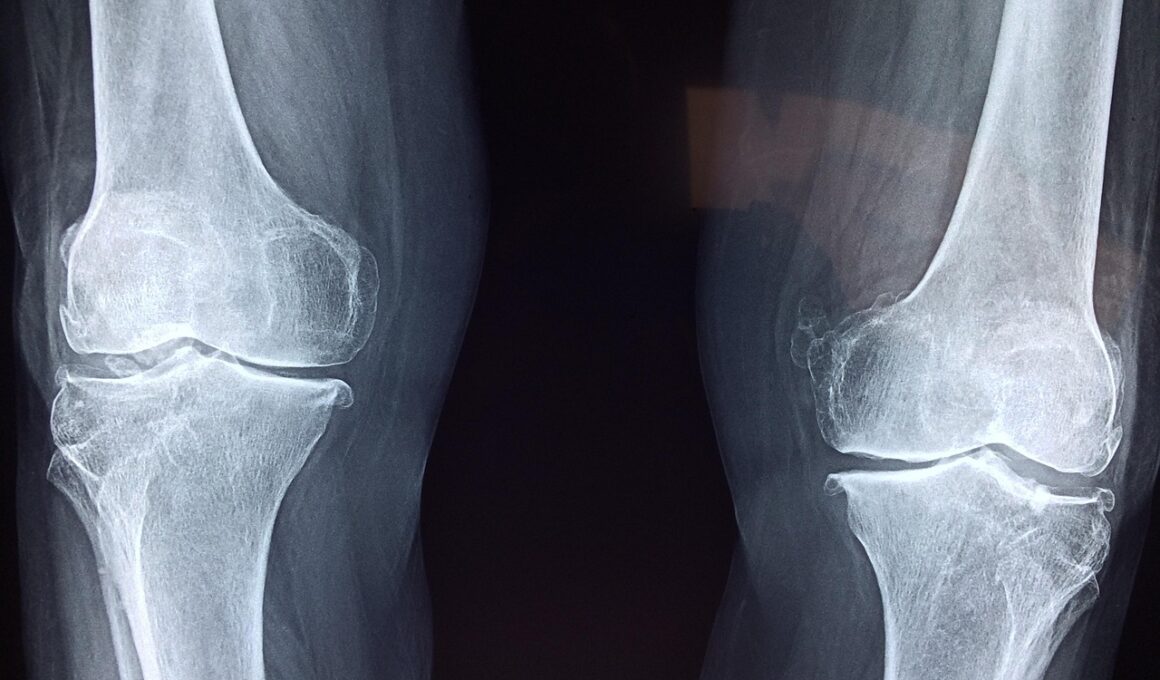

Understanding common joint injuries in bodybuilding will provide insights for injury prevention. Conditions such as tendinitis, bursitis, and arthritis can impact a bodybuilder’s routine significantly, and recognizing early symptoms is essential. Ignoring these symptoms can exacerbate the condition, leading to long-term joint damage. Tendinitis, for example, often occurs in the shoulder and elbow, where repetitive motions are common. Bursitis can lead to swelling pain, especially around the knees and hips. Ensuring your warm-up is thorough can minimize these risks effectively. To help visualize these concepts, consider regularly evaluating your body’s signals and logging any discomfort you feel. Listening to your body can prevent minor pains from escalating into serious injuries, giving your joints the care they deserve. Furthermore, consult professionals about your training regimen to understand how to adapt exercises based on your unique needs. Avoid pushing through pain, as it often signals impending injury. Taking a more adaptive approach can strengthen your joints while allowing for continued progress in your regimen without compromising health, especially for both novices and experienced bodybuilders alike.